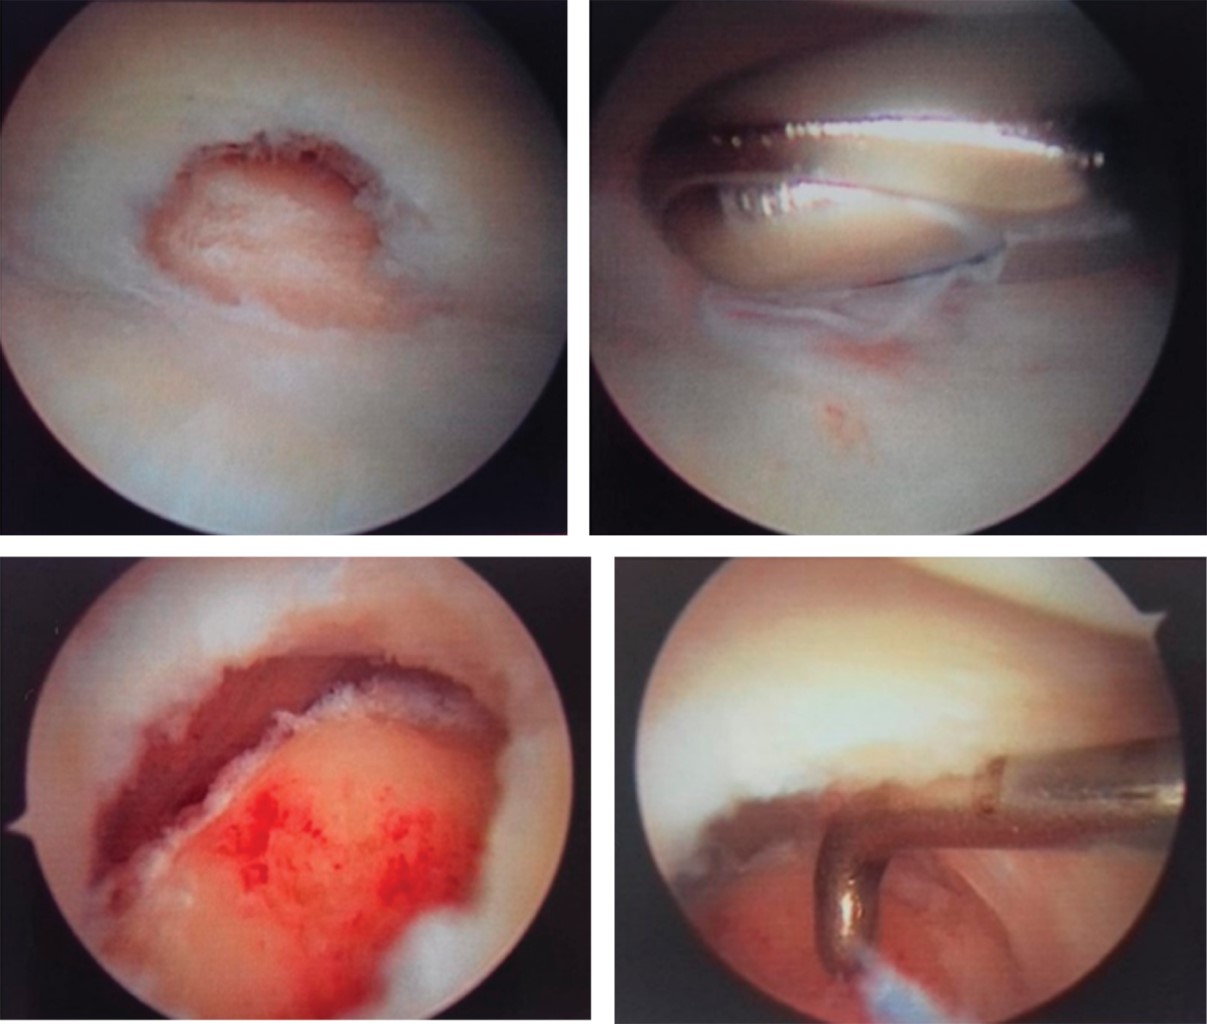

El artroscopio es introducido en portal 3-4 mediante técnica estándar, la salida de la solución fue obtenida colocando aguja hipodérmica número 18 a través del portal 6R o 6U. El recorrido artroscópico se realizó de rutina desde el portal mediocarpal hasta el portal cubital, visualizando sinovitis con ruptura central del fibrocartílago triangular (Figura 3).

Realizando procedimiento a través de portal 6R, desbridando la ruptura central del fibrocartílago triangular con rasurador mecánico 2.9 mm hasta dejar bordes estables, con fresa redonda 3.0 mm (Arthrex) es usada para remover todo el cartílago articular distal del cúbito, así como los quistes subcondrales a través del defecto central ante desbridado del fibrocartílago triangular. Con la misma fresa se realiza el acortamiento del extremo distal del cúbito, con el ayudante que realiza movimiento de rotación de la muñeca desde la supinación hasta la pronación completa, para así realizar una adecuada exposición y resección del cúbito distal mientras se protege la inserción del fibrocartílago triangular en la base del estiloide cubital.

Se realiza sinovectomía, se extraen los cuerpos libres articulares, se realiza hemostasia con ayuda de radiofrecuencia. Al final de la cirugía se obtuvo una varianza cubital de neutral a -2 mm, se cierran los portales con prolene 0000, y se inmoviliza con férula antebraquiopalmar.

Figura 2

Figura 3